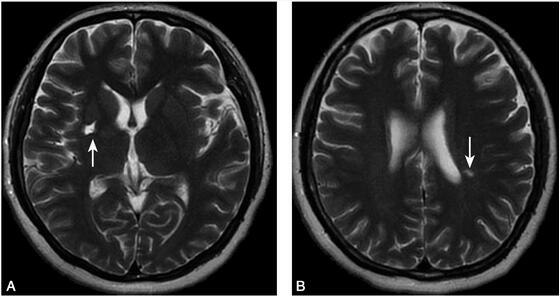

1小时条评论1 病例简介 患者女,25岁,蒙古族,以突发右侧肢体无力1个月余于2008年6月10日收入院。患者主诉于入院前1个月余午睡后出现右腿麻木,无明显无力,未在意,次日晨起时发觉右侧肢体麻木加重,自觉没有知觉,伴有右侧肢体无力,易摔倒,需要人扶持方能行走,无头痛头...

1小时条评论1 病例简介 患者女,51岁,以反复发作头昏、右侧肢体无力8年,伴随记忆力减退5年于2008年3月入院。 8年前无明显诱因出现头部不适感和头昏,不伴视物旋转、视物成双及耳鸣,不伴头痛、恶心及呕吐,次日患者出现右侧上、下肢无力,走路不稳,上述症状在住院治疗后出...